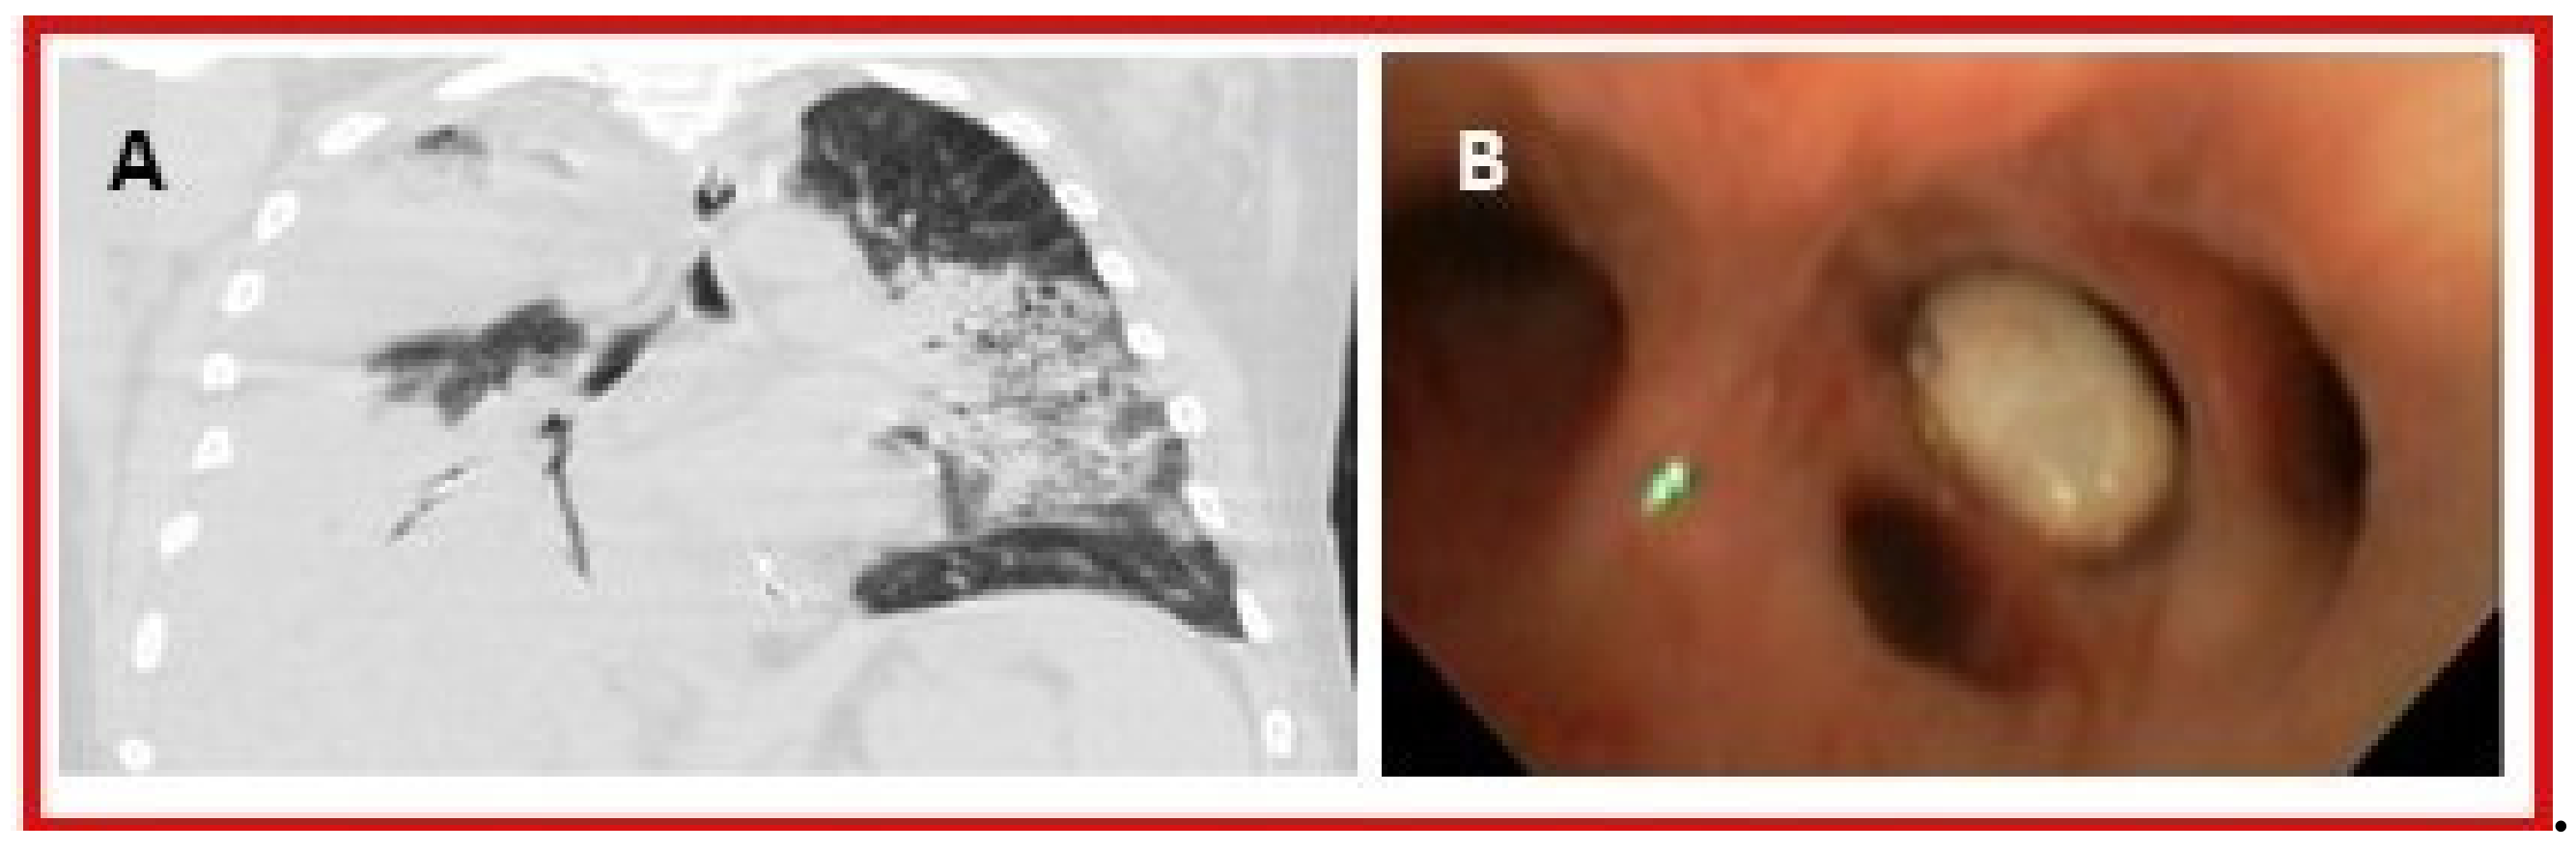

- Adamson, R.; Lacy, J.M.; Cheng, A.M.; Park, D.R. Tophus causing bronchial obstruction. Am. J. Respir. Crit. Care Med. 2013, 188, e72–e73. [Google Scholar] [CrossRef] [PubMed]

- Zang, Y.-S.; Fang, Z.; Li, B. Gout-associated lung disease. Rheumatology 2012, 51, 756. [Google Scholar] [CrossRef] [PubMed]